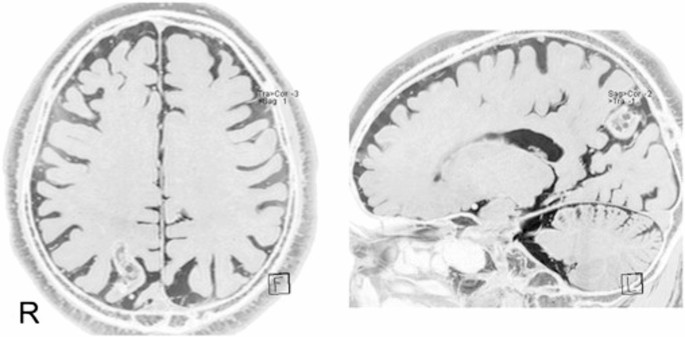

Seizure disorders have also been implicated in patients developing akinetopsia. Maeda et al. [12] described several cases of akinetopsia accompanied by abnormal brainwave patterns in the right hemisphere. One 68-year-old woman reported experiencing an uncomfortable feeling that her vision would freeze, lose color, and resemble a black-and-white photograph. This symptom had been recurring daily. Electroencephalogram (EEG) recordings revealed abnormal brain wave patterns in the right hemisphere, whereas single photon emission computed tomography (SPECT) scans revealed increased blood flow in the right frontotemporal region and decreased blood flow in the bilateral occipital regions. Before treatment, the patient manifested reduced blood flow in regions of the brain associated with motion and color perception, especially in the bilateral classical centers of motion (MT/V5) and color (ventral part of V4; V4v). One hypothesis is that epileptic impulses originating from the right frontotemporal region may travel backwards through the right ventral visual pathway and suppress the functioning of MT/V5 and V4v on the same side, resulting in a loss of motion and color perception. Maeda et al. [12] reported a case of epilepsy focused in the right frontotemporal region, as confirmed by EEG and SPECT results, that demonstrated full-field akinetopsia with achromatopsia. Sakurai et al. [14] described another case of akinetopsia symptoms concurrent with focal epileptic seizures in the right temporal and parietal cortices, including the MT/V5 area (Fig. 3). The remote inhibition of the bilateral MT/V5 and V4 via the right ventral visual pathway and callosal connection could account for this rare symptom.

Magnetic resonance imaging. The lesion is visible in the right parietal lobe. Image from Sakurai et al., 2013 [14]. Akinetopsia as epileptic seizure. Epilepsy & Behavior Case Reports, Volume 1, Pages 74–76. © 2013 The Authors. Published by Elsevier Inc. Available under a Creative Commons Attribution 4.0 International License. (CC BY 4.0). No changes were made